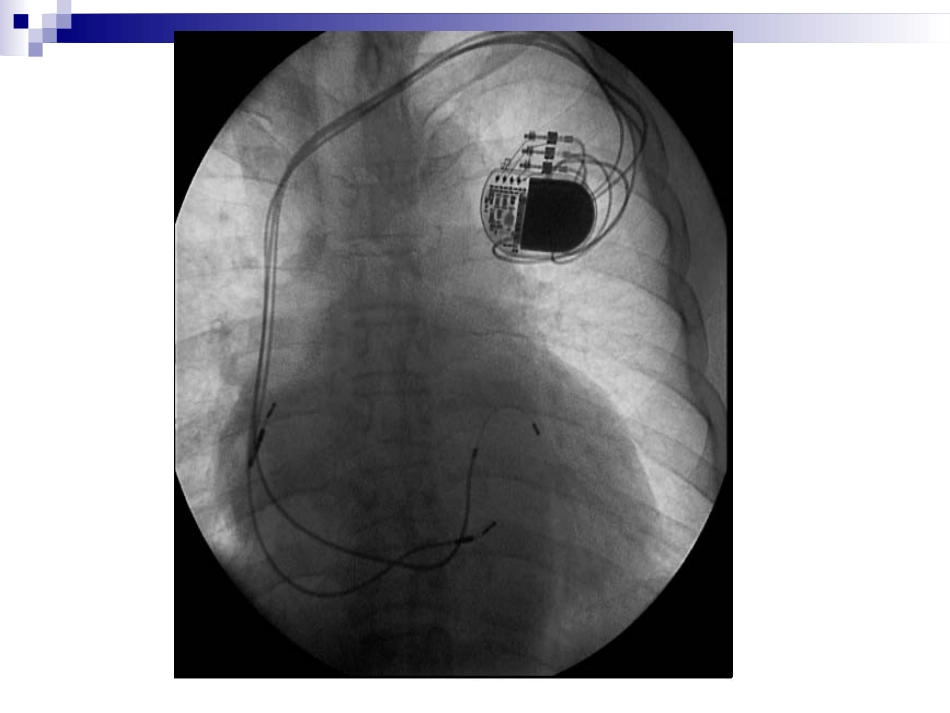

心脏起搏器心脏起搏定义人工心脏起搏(artificialcardiacpacing)是通过人工心脏起搏器或程序刺激器发放人造的脉冲电流刺激心脏,以带动心脏搏动的治疗方法。主要用于治疗缓慢心律失常,也用于快速的心律失常和治疗。什么是心脏起搏器?心脏起搏器由脉冲发生器、导线和电极组成。脉冲发生器呈扁圆形,体积非常小,大约有40506毫米,重量约30克。它实际上是一个微型计算机,由高性能电池提供能量。起搏器通常埋植在上胸部的皮下,它的导线通过静脉到达心脏,导线顶端的电极固定在心脏的内侧面心肌上。起搏器工作时,脉冲发生器发出的电脉冲,经导线、电极传到心肌,心肌感受到电脉冲刺激产生收缩。同时,起搏器电极也将心脏的电活动收集起来存入脉冲发生器内的芯片内,以便进行分析。人工心脏起搏器工作原理:监测心电、电激心脏临床上广泛应用的人工心脏起搏:就是用低能量电脉冲暂时或长期地刺激心脏,使之发生激动,以治疗严重心动过缓,心脏起搏也可用以终止或控制室上性和室性快速心律失常,称为抗心动过速起搏。心脏起博器的功能能替代或补充正常激发和控制心脏收缩的生理电子系统。它通过周期性发放的电脉冲刺激心脏,引起心搏,并实现生物机能控制。n如果心脏原有的起搏点丧失其作用而使冲动形成受扰,或者心脏固有的传导系统不能正常工作(如窦性停止、窦房阻滞、窦性心动过缓或某心房、心室出现异使节律,以及心动过速等),起搏器能帮助心脏恢复、接近正常功能。特别是对那些药物疗效不佳,甚至于治疗无效的心脏病患者,人工心脏起搏器在临床上获得了成功。绝大多数起搏器具有四个功能刺激心脏使它除极感知心脏自身电活动对增加的新陈代谢需求作出反应,提供频率适应性起搏提供由起搏器存储起来的心电诊断信息心脏起搏器的临床应用长期起搏房室传导阻滞三束支阻滞伴心脑综合症病态窦房结综合症临时性起搏指心脏病变可望恢复,紧急情况下保护性应用和诊断应用的短时间使用心脏起搏诊断:还可用于某些疾病的诊断。例如心房调搏辅助诊断可疑的冠心病、心房超速起搏法诊断窦房结功能不全,预测完全性房室传导阻滞患者是否有发生心脑综合症的危险等。药理及实验研究:人工心脏起搏技术在心血管的生理和病理生理以及药理和临床应用的实验研究工作中,也取得了发展。例如在心律失常方面,将逐步揭示一些我们还不能解释的电生理现象,对心律失常的诊断和治疗会起到更积极的作用。永久性与临时性心脏起搏器埋藏于体内的起搏器为埋藏式起搏器,作为永久性心脏起搏,用于慢性或间歇发作的严重缓慢性心律失常如心脏传导阻滞、病态窦房结综合征等;放在体外的起搏器为体外起搏器,用于临时性起搏,如永久性起搏器植入的过渡或心脏骤停的抢救等等。临时起搏的适应征1.急性前壁心肌梗塞伴有Ⅲ度或高度房室传导阻滞,或下壁梗塞伴有Ⅲ度或高度房室传导阻滞经药物治疗无效者。2.急性心肌炎或心肌病伴有阿斯综合征者3.药物中毒引起的心动过缓,并发阿斯综合征者.4.心脏手术后发生的Ⅲ度房室传导阻滞者5.电解质紊乱,如高血钾引起的Ⅲ度房室传导阻滞者。6.超速起搏用以诊断及治疗其他方法所不能解决的室上速或室性心动过速。7.保护性应用于更换永久起搏导管前,冠脉造影,电击复律,外科手术等。强干扰信号对起搏器的影响当患者处于较强的50Hz市电或高频强电磁场干扰的环境中时,如果这些干扰信号很强,频率远高于起搏频率,这些干扰信号和感知的R波一样,能使按需功能控制器的单稳态电路提前触发;脉冲发生器在干扰信号存在的时间内一直处于抑制状态,致使起搏器停止发放起搏脉冲,从而使患者失去人工心脏起搏。解决方法?解决方法保持在强干扰存在的条件下,把强干扰信号衰减,使之不能触发按需功能控制器,失去对脉冲发生器的抑制作用,脉冲发生器按自己固有频率发放起搏脉冲,起博器转换为固定式工作,其起搏频率稍快于按需型(这是扣除按需型的反拗期的结果)。强干扰一旦消失,起搏器又能自动恢复到按需工作状态。具体如何实现?最高起搏频率限制电路患者安装起搏器后的心率多数是依赖起搏器的工作频率,如果起搏器因电源、元器件变质或损坏而造...